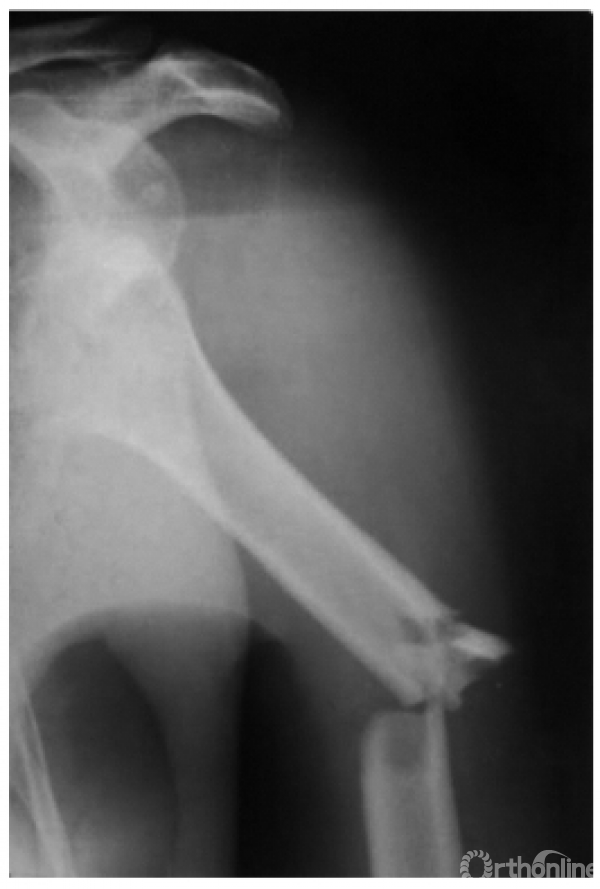

例1:肩关节外脱位并肱骨外科颈骨折,肱骨头上下倒置,远折端回缩至关节盂处致形成假关节(如下图)。